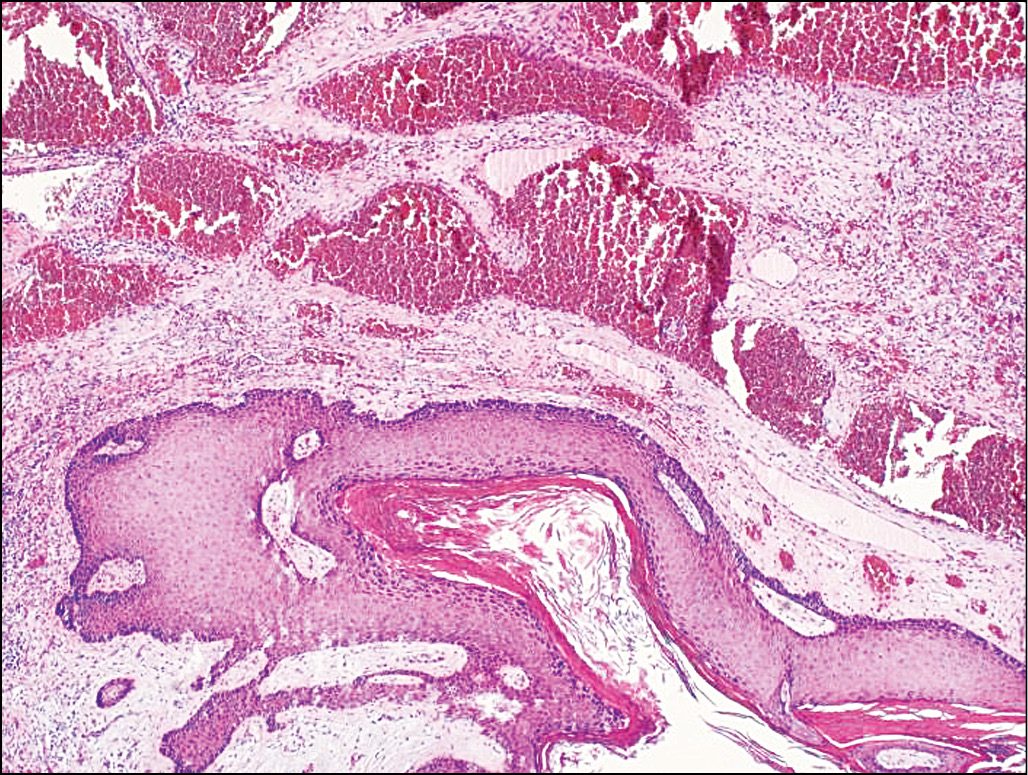

Дерматоскопическая картина представлена молочно-красными гомогенными зонами, белыми перемычками и зоной изъязвления (рис. 4, б). Патоморфологическое заключение: дольчатая капиллярная гемангиома (пиогенная гранулёма) кожи (рис. 5).

Рис. 5. Гистологический препарат. Опухоль с прилежащими тканями. Гиперплазия эпителия над опухолью. Расширенные полнокровные капилляры опухоли. Окраска гематоксилином и эозином. Ув. 50.